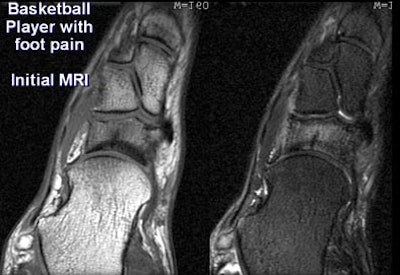

In his presentation, Gold used several case studies from Stanford to illustrate his assessments. First up, a basketball player with foot pain.

CT (0.5-mm reconstructions) revealed only subtle sclerosis of the navicular bone. But MRI showed a region of low signal on T2- and T2-weighted images, surrounded by marrow edema within the navicular bone. "In this case MRI is still somewhat more sensitive (for occult fracture) probably due to the presence of marrow edema," Gold said.

| In a basketball player presenting with foot pain, MRI (below) was better able to show an occult fracture of the navicular bone. All images courtesy of Dr. Garry Gold. |